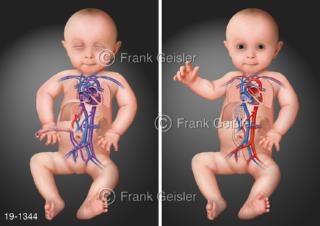

Bilder zu Medical Art und Anatomie-Art, visuelle Darstellung medizinischer Inhalte künstlerisch umgesetzt, medizinisches Fachwissen als künstlerische Gestaltung für die Ausbildung, zur Patientenaufklärung und zur wissenschaftlichen Kommunikation, als künstlerische Dekoration in Gesundheitseinrichtungen und Arztpraxen

© MediDesign Frank Geisler